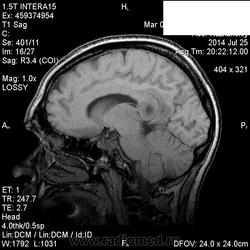

Мама приятельницы.Нарушение походки в течение 2-3 месяцев.

DDs: рассеянный склероз, токсоплазмоз, mts.

Рассеянный склероз вряд ли. Я бы добавила лимфому и глиобластому.

Думается больше о глиобластоме в форме бабочки. Из книги "Диагностическая нейрорадиология". Корниенко, Пронин.

На РС точно не похоже. Токсоплазмоз - навряд ли, т.к. "мама приятельницы", а это чаще всего бывает у ВИЧ-инфицированных.

+1 к глиобластоме.

Да, больше данных за опухоль.

Сегодня узнала: нейрохирурги за лимфому.Сделали КТ и подтвердили .